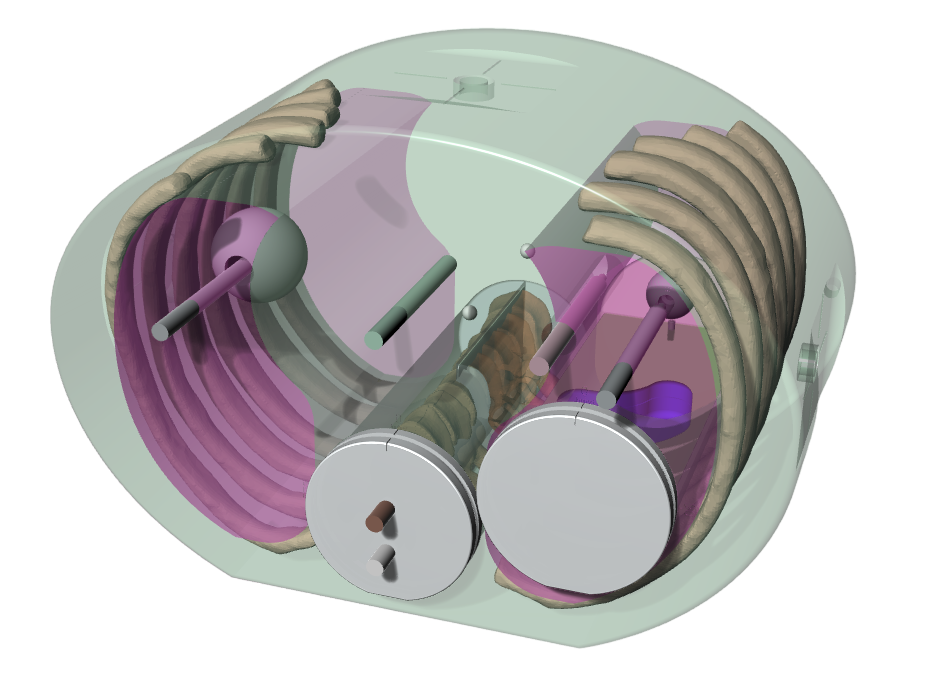

The End-to-End SBRT Phantom is a single tool for high-accuracy end-to-end commissioning and routine QA necessary for the high dose per fraction associated with SBRT deliveries.

Proven Tissue Equivalence

Linear attenuations of the simulated tissues are within 1% of actual attenuation for water and bone, and within 3% for lung from 50 keV to 15 MeV. The phantom contains a 3D anthropomorphic removable spine with cortical and trabecular bone as internal landmarks

The E2E SBRT Phantom contains multiple targets and alignment marks for verifying that imaging, localization, and targeting systems are aligned. This is a critical need for accurate delivery of these high-dose treatments.

Three OSL pockets in the right lung provide high-resolution dosimetry measurements to the target and spinal cord in a single delivery.

The removable split spine allows for film measurements in the sagittal orientation in the inferior half of the spine rod. Film can also be placed in the sagittal slice in the spine and lung inserts.